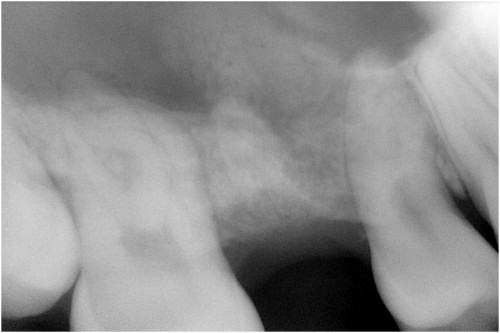

術前

被せ物の二次虫歯と根の破折

抜歯後

抜歯後2ケ月後経過

抜歯後4ケ月半後経過

インプラント埋入

ピエゾサージェリー

インプラント埋入後

オペ時のISQ値

土台装着

被せ物装着

術後